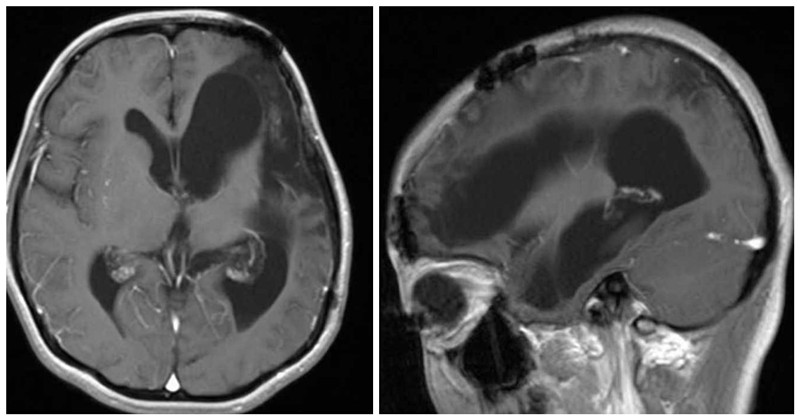

2022年起,17岁少女小潘开始反复出现左侧颞部胀痛,还伴随着头晕。这些症状呈阵发性,不过能自行缓解,起初并未引起她和家人的太多重视。后来,头晕头痛的症状愈发严重,恶心呕吐频繁出现,记忆力和语言表达能力也明显下降,学习成绩更是一落千丈。2023年的一天,家人带她到医院就诊。经过详细的检查,头颅核磁共振检查显示,左侧额颞顶部巨大占位性病变,初步考虑为脑膜瘤。这个消息,犹如晴天霹雳,让小潘和家人陷入了无尽的担忧与恐惧之中。

患者术前核磁共振

小潘的病情牵动着神经外科医护人员的心,从核磁共振检查结果上看,这颗肿瘤达到成人拳头大小,犹如一颗“定时炸弹”,埋在小潘的头部,也悬在神经外科医护人员的心上。因肿瘤较大,脑组织受压明显,手术难度极大,但神经外科团队没有丝毫退缩。在科室主任李松年主任医师的指导下,池超超副主任医师扛起主刀重任,他们反复研究病情,制定了周密的手术方案。